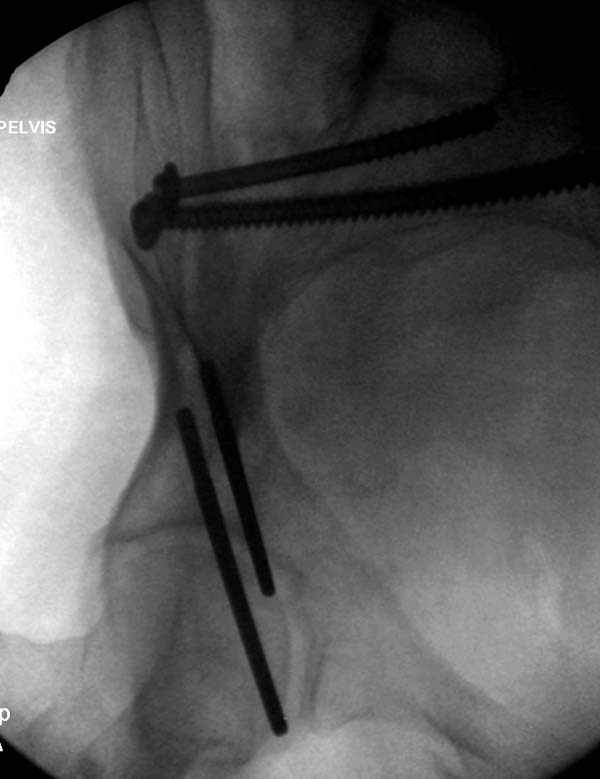

Здесь снимки, которые показывают направление стержня, а также идею

репозиции вытяжением. На рентгенопроницаемых столах имеется возможность

установить дополнительную раму, где по желанию можно увеличить или

уменьшить высоту угла вытяжения. Для репозиции таза больной в положение

на спине, стержень для вытяжения остается во время операции. Система

подойдет для тракции головки бедра из вертлужной впадины, и для этого

стерильная веревка и Synthes Universal Chuck with T-Handle.

Двухстороннее повреждение крестца и травматическая ампутация бедра, где

неопытной бригадой дежурантов установлен верхний наружный фиксатор для

стабилизации. На третий день ревизия на более стабильный, и

окончательная фиксация. Первые снимки после стабилизации таза, и другие,

где показаны (параллельные) правильная установка на AIIS т.е на месте

прикрепления прямой мышцы бедра. Ампутация закончена костно пластическим

методом.